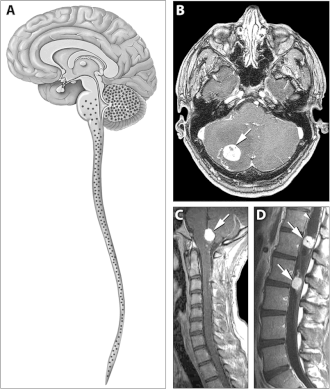

Болезнь Гиппеля — Линдау (цереброретинальный ангиоматоз, англ. Von Hippel–Lindau disease — VHL) — факоматоз, при котором гемангиобластомы мозжечка сочетаются с ангиомами спинного мозга, множественными врождёнными кистами поджелудочной железы и почек. У четверти больных развивается карцинома почки, часто первично-множественная. Симптомы заболевания становятся очевидными во 2-м десятилетии жизни — одним из первых обнаруживается кровоизлияние в глазное яблоко или в заднюю черепную ямку с признаками внутричерепной гипертензии или мозжечковыми расстройствами. У большинства пациентов в цереброспинальной жидкости обнаруживают повышение содержания белка, у половины детей с опухолями мозжечка — увеличение числа клеток.

Часто отмечаются гемангиомы сетчатки. Вследствие нарушения проницаемости стенок капилляров в них может накапливаться суб- и интраретинальный экссудат, содержащий липиды. В поздних стадиях болезни развивается экссудативная отслойка сетчатки.